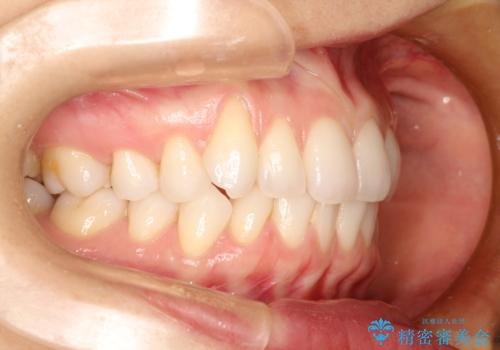

右上の犬歯の歯茎は矯正前から退縮を起こしていましたが、矯正後もその退縮に関しては変化がありませんでした。今回は患者様が歯肉退縮に関しては治療をご希望ではありませんでしたが、当院ではこのように歯茎が下がり露出した根面を、歯茎を移植することでカバーし見た目を改善する手術を行っています。